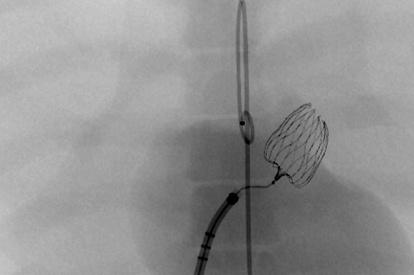

ASD-PFO Closure Module

LAA Closure Module